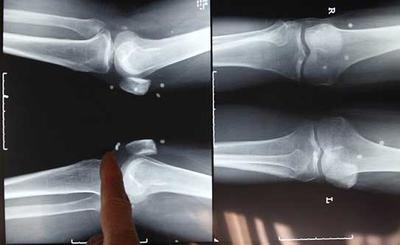

Pearls embedded in man's leg

Chinese doctors in Changsha have removed 42 pearls from the body of a 61 year old man Zou Feng, of Hunan province .

Doctors removed pearls from his waist, hips and legs.The surgery was performed last week.

Zou Feng had pearls embedded into his body in 2011 in a bid to rid him of his severe leg pain.